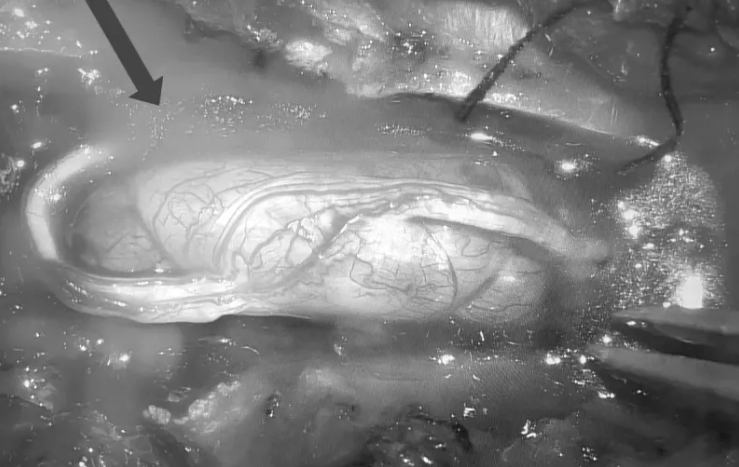

TS Nguyễn Khắc Hiếu,khoa Ngoại Thần kinh,cùng êkíp vi phẫu thành công loại bỏ hoàn toàn khối u tủy kích thước 1,5 x 2 cm trong ống sống ngực bệnh nhân. Hậu phẫu,hai chân bệnh nhân phục hồi vận động,lấy lại cảm giác,năm ngày sau có thể đi lại nhẹ nhàng.

Hình ảnh chụp MRI khối u tủy trong ống sống ngực của bệnh nhân. Ảnh: Bệnh viện cung cấp

Bác sĩ Hiếu đánh giá đây là một ca khó,bệnh diễn biến cấp tính và dễ nhầm với bệnh lý khác. Khối u không lớn nhưng nằm ở vùng tủy ngực là nơi ống sống chật hẹp,chỉ cần một tác động nhỏ khi phẫu thuật cũng có thể gây tổn thương tủy.